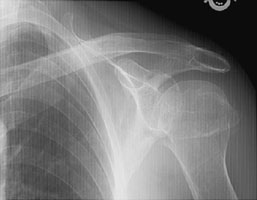

- Click on the image for a larger versionCAP radiograph of the right shoulder. This depicts fractures of both tuberosities and a surgical neck fracture (Neer four-part).